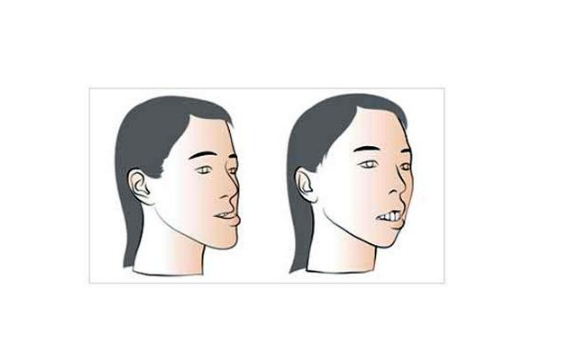

牙顎畸形圖片

牙槽骨突出